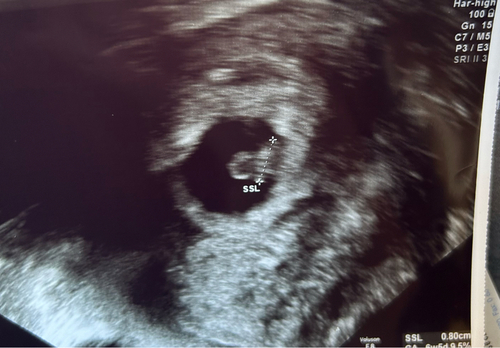

14+6 🥰 mit Elle, Speiche und Hand :)